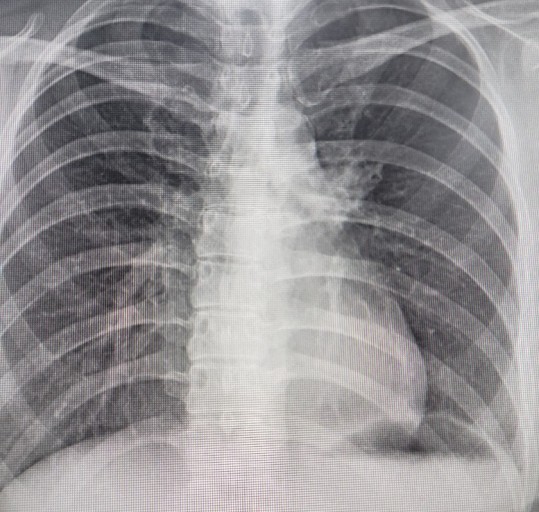

폐암은 위암, 갑상선암 다음으로 3번째로 발병 빈도가 높은 3대 암 중 한 가지인데요. 폐암은 재발과 전이까지의 빈도도 잦은지라 완치가 어렵다고 하며 폐암 발병 초기에는 거의 증상이 없을 수가 있어 수술이 불가능한 3기, 혹은 4기에 주로 진단된다고 해요.

폐암 초기증상 폐암 4기에 이르게 되면 5년 생존률이 30% 대로 감소하게 된다고 해요. 그리하여 폐암은 암 질병이자 중 사망자 비율이 가장 높은 것으로 나타나고 있어요.

폐암은 사망률 2위를 차지하고 있는 간암에 비해 무려 2배에 가까운 사망률을 보이고 있다고 합니다. 이렇게 치명적인 폐암에 대해 미리 알고 대처하는 것이 바람직할 것 같아요. 아래에서는 폐암이라 판단해 볼 수 있는 그 초기증상에 대해 간단히 설명드릴게요.